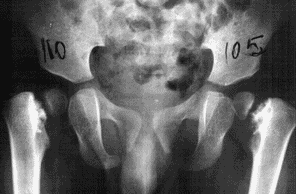

Dalla misurazione dei radiogrammi del bacino, l’angolo di inclinazione cervico-diafisaria è pari a 90° a sinistra e 99° a destra. Questo configura la diagnosi di coxo vara bilaterale. Dall’esame radiologico della colonna si rileva una displasia di D10 e D11, con una deformità a cartuccia di carabina dei corpi vertebrali. Inoltre, il valgismo tibiale (dunque non soltanto funzionale) appare correlato a una displasia dell’epifisi superiore della tibia.